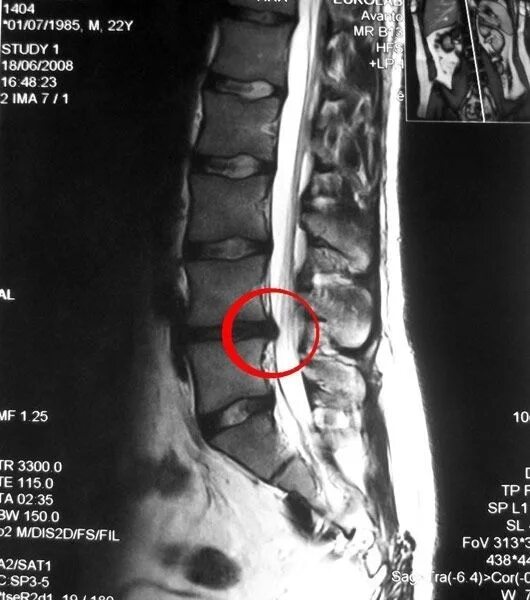

Грыжа диска мрт